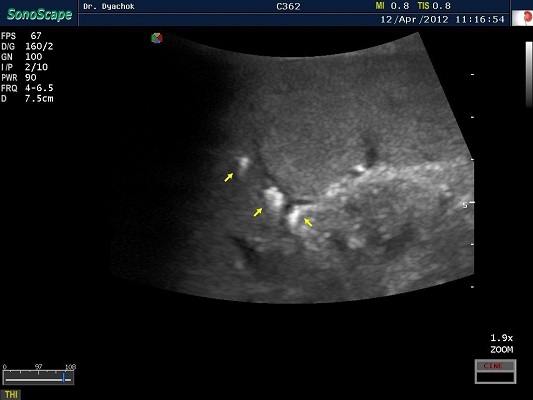

SonoScape S2N Vet – уникальная узи-система, выполненная в виде портативного ноутбука для легкой переноски. Отличается эта система цветным форматом визуализации, а также крайне чувствительными доплеровскими режимами, работающими на уровне премиальных аппаратов. При оптимальной цене – это очень хорошее и сбалансированное решение для ветеринарной клиники.

Диагональ монитора составляет 15,6 дюймов, что обеспечит комфортную работу для врачей и полный спектр визуализации для пациентов. Компактный вес не превышает 5 кг. (вместе с батареей), что оценят выездные бригады скорой помощи или ветеринары, выезжающие на дом.

Цифровая рабочая станция S2N Vet предполагает наличие жесткого диска для записи данных, составление и экспорт отчетов с возможностью добавления изображений, ведение базы данных пациентов.

Данный аппарат является незаменимым помощником в диагностической медицине. Ему нет конкурентов по оснащению, компактности и цене, а значит пора сделать правильный выбор для вашей клиники.